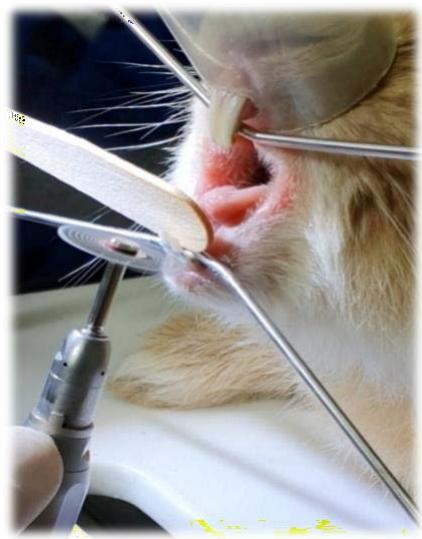

No dia 13 de Setembro de 2021 no Hospital Veterinário Jefferson Ricardo, situado em João Pessoa, Paraíba, o paciente foi operado. O tratamento consistiu na redução da coroa clínicados incisivos por meio de odontosecção com disco de corte diamantado (Fig. 11 e 12) e dos pré molares e molares usando a peça reta com uma broca carbide esférica ${ \mathsf { n } } ^ { \circ } \ 8,$ buscando a oclusão correta dos incisivos, que acontece quando os incisivos inferiores se encontram entre os incisivos superiores anteriores e posteriores e uma angulação próxima dos $10 ^ { \circ }$ para os pré molares e molares, que é o preconizado na literatura VESTRAETE, Frank (2005). Essa verificação foi feitapor meio do registro fotográfico utilizando-se uma micro câmera anexada ao celular e também uma câmera digital (Fig. 13, 14 e 15 a,b,c).

Fig. 12: Odontosecção dos incisivos inferiores

Fig. 11: Demarcação do local da ondontosecção com caneta cirúrgica